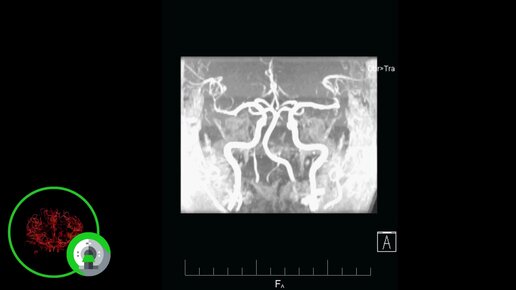

Что покажет МРТ сосудов головного мозга (видео)